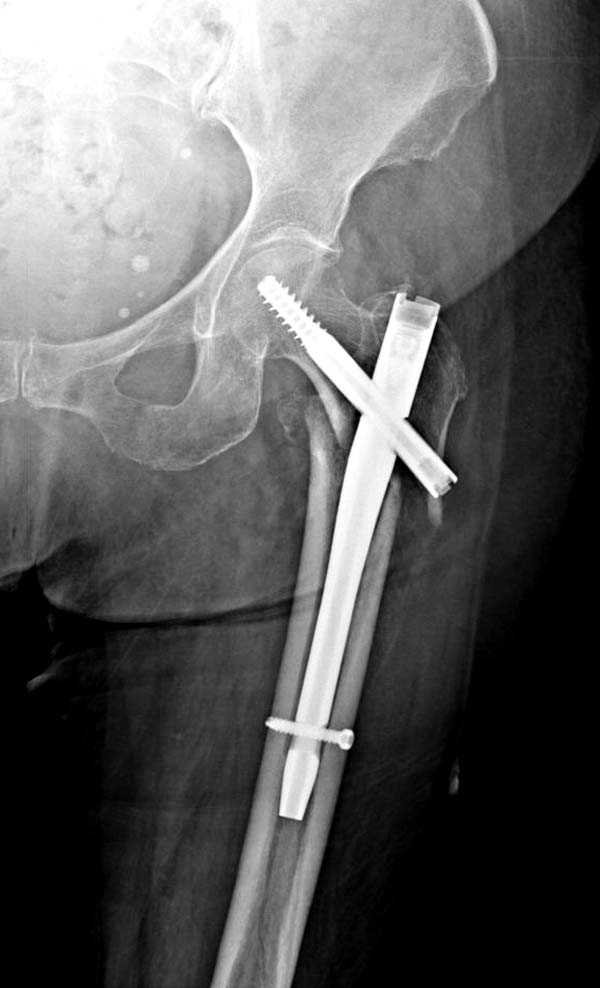

При первом послеоперационном поликлиническом осмотре больная предъявила жалобы на боли в бедре. В серийных снимках обнаружен продольный перелом верхнего отдела бедра.

Считаем, что техническая ошибка произошла во время установки гвоздя, когда рассверливанию канала не уделили должного внимания. Канал остался узковат, и гвоздь был забит с силой. Полная нагрузка конечности приостановлена на две недели, и боли в конечности изчезли. Больная начала нагрузку и перелом срастается.-- Djoldas Kuldjanov, M.D.Associate ProfessorDepartment of Orthopedic SurgerySt. Louis University

Мне тоже представляется, что это не единственная проблема. Продольные трещины заживают легко и быстро. Интересно, почему увеличился варус и

появилась медиализация дистального отломка.

Мне думается, что варусное положение проксимального отломка на последующих снимках не более чем проекционный феномен. Раскол же диафиза вдоль, наверняка, связан с чрезмерно насильственным введением штифта. Вообще, при реверсивных, да и обычных вертельных переломах, многие давно отказались от короткой Гаммы в пользу long-версии. Но в любом случае надо быть на 100 уверенным в подготовке канала.

Перелом А3, подвертельный, вероятно, на длинной версии гвоздя такого бы не произошло

eto nestabil'nui perelom. nado bylo stavit' gamma long. kanal uzkii (bylo vidno). mesiaz ne nagrujat', vse srastetsia!